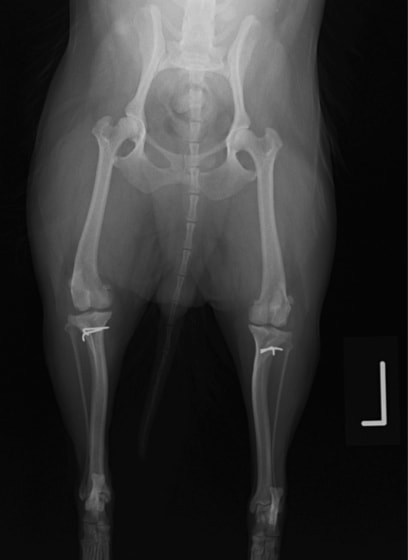

■ 症例20 ポメラニアン 8ヶ月 1.8kg

左右膝蓋骨脱臼 グレードⅢ

2ヶ月前から間欠的跛行が認められ、両膝の膝蓋骨脱臼整復術を行った。

手技は縫工筋及び内側広筋の解放、脛骨粗面の外側転位、滑車ブロック形造溝術、内外側関節包の縫縮を選択し実施した。

右側の膝蓋骨脱臼は上記手技で整復されたものの、左側はそれのみでは膝蓋骨が浮く様子が認められた。その為、PDS縫合糸にて膝蓋靱帯を1糸のみ縫合し、靱帯の縫縮を行った。

膝蓋骨脱臼は膝関節における膝蓋骨の内外側の脱臼と定義されるが、時として単純な内外の脱臼ではなく、膝蓋骨が大きく前方に浮き上がるように脱臼する場合がある。特にトイプードルやポメラニアンといった犬種に多く認められる。

内側脱臼に加えて前方への浮き上がりを矯正する為に、従来より脛骨粗面転移により膝蓋靭帯を外方と下方に引っ張り、固定する方法を選択する。膝蓋骨の前方への浮き上がりが軽度の場合は、従来法ではなく関節包の縫縮で対応していた。しかし、一部の症例で膝蓋骨の動きが悪くなり伸展機構が円滑に機能せずロボット様歩行になるケースがあった。

その為、膝蓋靭帯自体を縫縮する方法を採用した。この方法により、膝関節の伸展機構を妨げず膝蓋骨の軽度の浮きを矯正することが可能となった。

本症例の経過は良好である